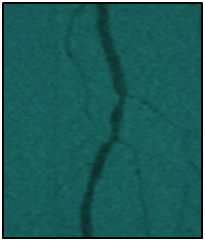

Endovascular procedure was done with antegrade access in the ipsilateral common femoral artery, diagnostic angiography confirmed: Patency of the femoral-popliteal axis, occlusion of the posterior and anterior tibial arteries, two critical stenotic lesions in the fibular artery and revascularization of the dorsalis pedis and plantar arteries by the fibular artery. To treat the fibular critical atherosclerotic lesions were performed a percutaneous transluminal angioplasty using a 0.0018in.guidewire, catheter support and a catheter balloon (3,0x6 mm and 3,5x 15mm).

Final angiographic control showed patency of the fibular artery and dorsalis pedis, with direct flow for the first metatarsal artery, thus guaranteeing enough flow to heal the ulcer in six months after the procedure. In conclusion endovascular treatment has a high technical eligibility with good reported outcomes and represents an alternative for diabetics with CLI Disease (Figure 1 and 2).

• Figure 1 Angiography from left to right showing femoral-popliteal axis, occlusion of the posterior and anterior tibial arteries, in detail two critical stenotic lesions in the fibular artery.

• Figure 2 From left to right showing percutaneous transluminal BTK balloon angioplasty, and revascularization of the dorsalis pedis and plantar arteries by the fibular artery.